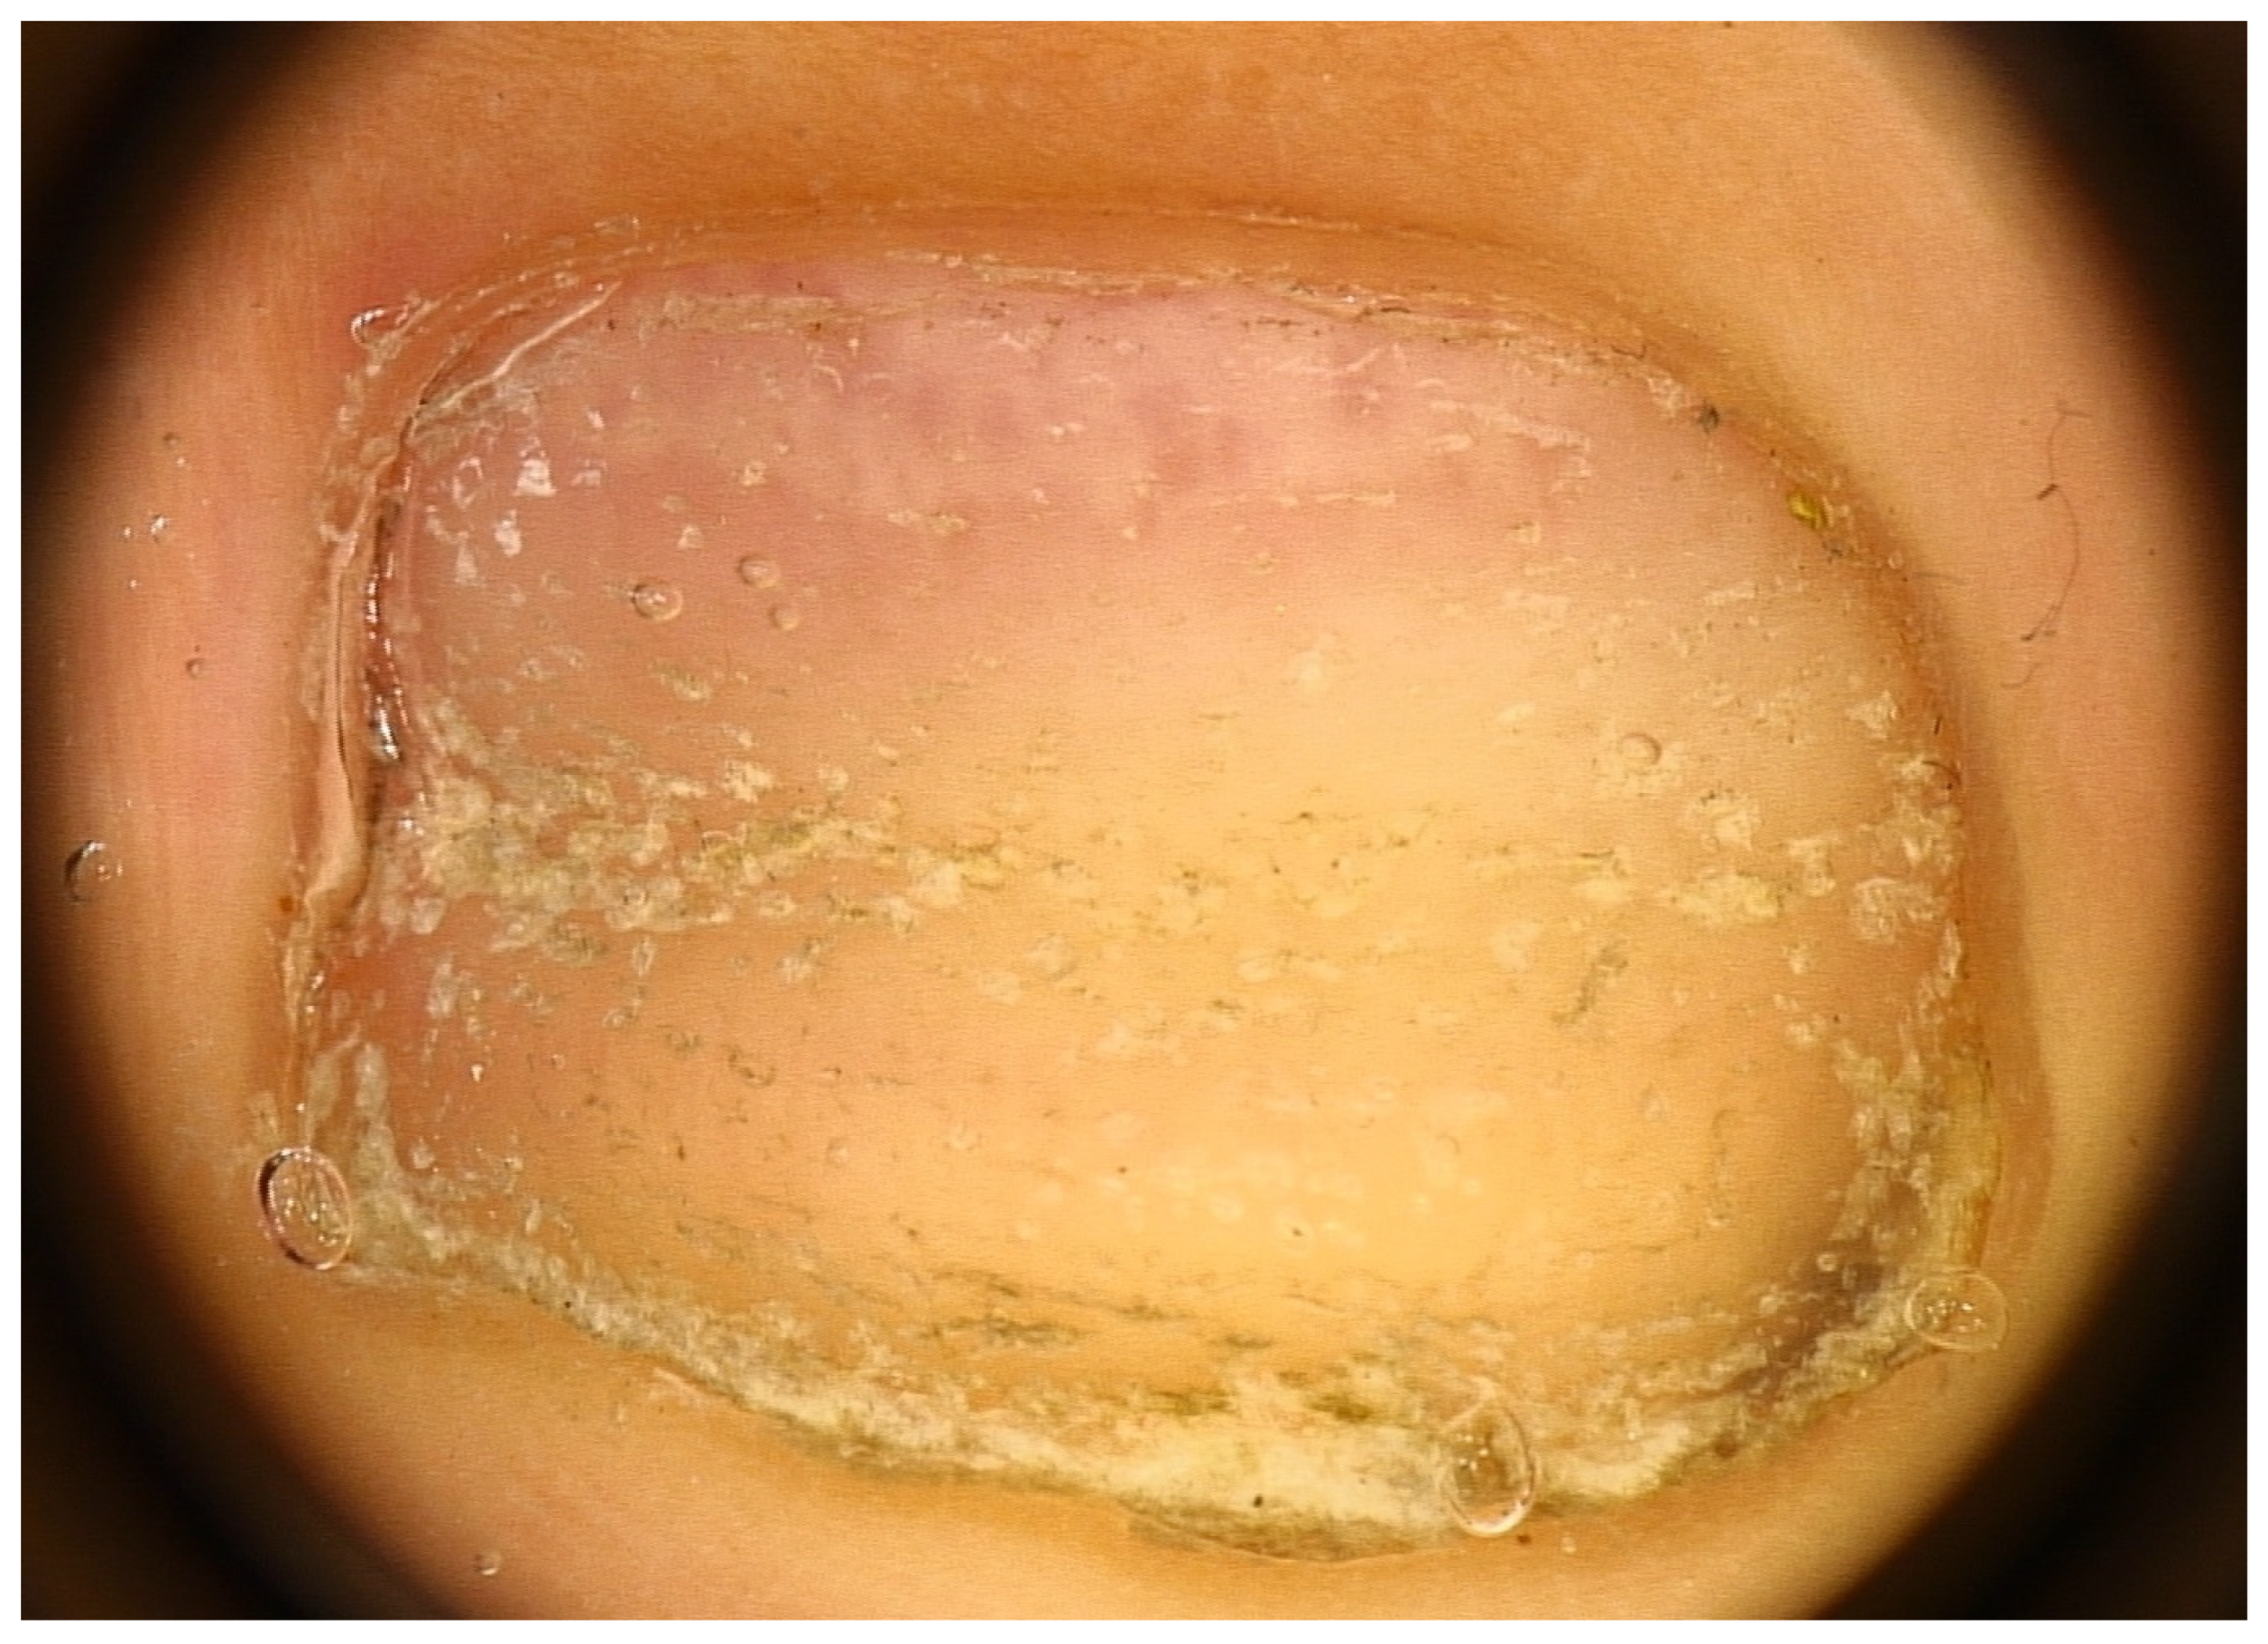

Another nail change seen in AA nails is the red lunula. Note that the lunula (distal and visible part of the matrix) is most prominent on the thumb and great toe and may be partly or completely concealed by the proximal nail fold in other digits. The normal lunula has a white hue. In AA, islands of red color resembling the color of the nail bed may appear in the lunula, giving rise to a motheaten appearance (mottled lunula) with unaltered margins [37] (Figure 6). These red spots are attributed to dilated and tortuous vessels in the superficial papillary dermis of the distal matrix [38,39]—probably systemic or local factors are responsible for angiogenesis within the nail unit. The red lunula is not, however, a specific and diagnostic sign, as it is seen in many other diseases. At least for pediatric patients, literature reports red-mottled lunula only in association with pitting and AA universalis [10], sometimes even in association with Beau’s lines only [40]. In adult patients, an association with AA severity was also found, occurring almost exclusively in AA universalis [12,22,40].

Figure 6.

Red lunula—islands of red color resembling the color of the nail bed may appear in the lunula, giving rise to a motheaten appearance (mottled lunula).